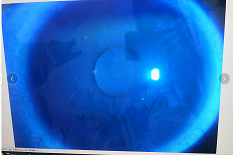

圓錐角膜要做那種治療比較好

圓錐角膜的治療應該依據(jù)角膜發(fā)展的時期選擇。目前圓錐角膜按照臨床癥狀大致可以分為四個時期,分別為潛伏期、初發(fā)期、完成期和瘢痕期,各個時期的主要癥狀表現(xiàn)如下:

完成期:發(fā)展迅速,角膜明顯前突,視力銳減。

瘢痕期:角膜急性角膜水腫、混濁,消退后基質層殘留瘢痕。